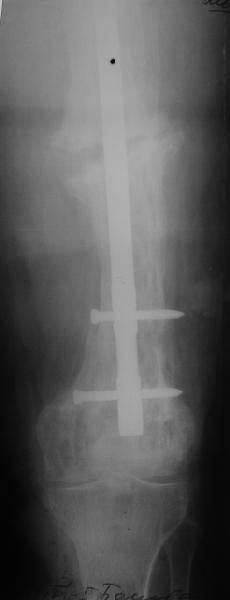

Пациент 82 лет, поступил через 5 мес. с несросшимся переломом после открытого интрамедуллярного остеосинтеза. Выполнили реостеосинтез стержнем 12 мм. ( мах. доступного нам в 2003 г.) Через 4 мес динамизация. В течении 2х лет сращения нет, тем не менее конечность опорна (ходит с тростью). От очередного реостеосинтеза отказались из-за сопутств. патологии.

Еще один пример. Пациентка с юга России, прислала рентгенограммы через год. На сегодня прошло 2 г. 8 мес. после операции. Несмотря на не очень убедительный процесс сращения, пациентка ходит. Учитывая остеопороз при Педжете, решили, что динамизировать вообще не нужно.

При переломах на фоне болезни Педжета металлоконструкция часто служит эндопротезом, несущим нагрузку. Динамизация индивидуальна,- по рентген-динамике. Основной упор- на медикаментозную терапию- см. канд. дисс. Колондаева А.Ф.

Стержень можно было бы поставить подлиннее.